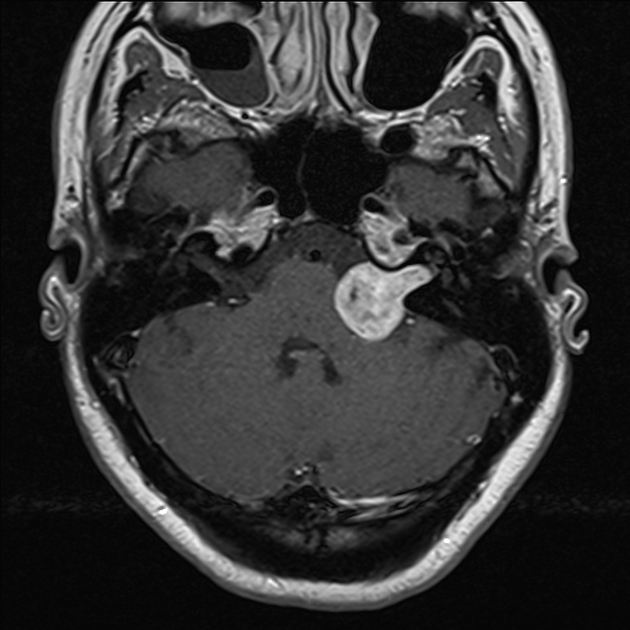

A patient presents with unilateral sensorineural hearing loss and the MRI findings are as shown. What is the most probable diagnosis?

Explanation: ***Acoustic neuroma*** - **Unilateral sensorineural hearing loss** is the classic presenting feature of acoustic neuroma (vestibular schwannoma), arising from the **8th cranial nerve**. - MRI typically shows **contrast enhancement** in the **cerebellopontine angle (CPA)** and **internal auditory canal (IAC)** with the characteristic **ice-cream cone** or **trumpet sign**. *Astrocytoma* - Primarily occurs within the **brain parenchyma** rather than the cerebellopontine angle or internal auditory canal. - Usually presents with **increased intracranial pressure**, **seizures**, or **focal neurological deficits**, not isolated hearing loss. *Glioma* - Represents **intraparenchymal brain tumors** that typically arise from **glial cells** within the brain tissue. - Clinical presentation involves **headaches**, **seizures**, and **progressive neurological deficits**, rarely causing isolated unilateral hearing loss. *Secondaries in the brain* - Brain **metastases** typically appear as **multiple lesions** with significant **surrounding edema** on MRI. - Usually associated with a **known primary malignancy** and systemic symptoms, not isolated cranial nerve dysfunction.